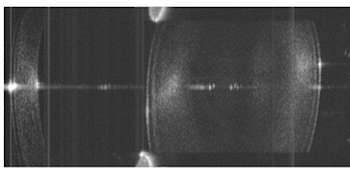

OCT image of the eye's anterior segment

Use of the same technique to image the whole eye has proved challenging. OCT's limited imaging depth can be improved though Fourier domain methods and use of modern swept-source laser sources, but the optics of the eye prevent the focusing of light on both the anterior chamber and the retina simultaneously without sacrificing resolution.

Quasi-simultaneous imaging of the whole eye was achieved using the retinal imaging configuration, but moving the ETL and offset lens further back to provide greater beam divergence. From that position, the resulting beam at the pupil plane could be either collimated (via low ETL current) or focused (high ETL current), with images of the anterior segment and retina acquired alternately.